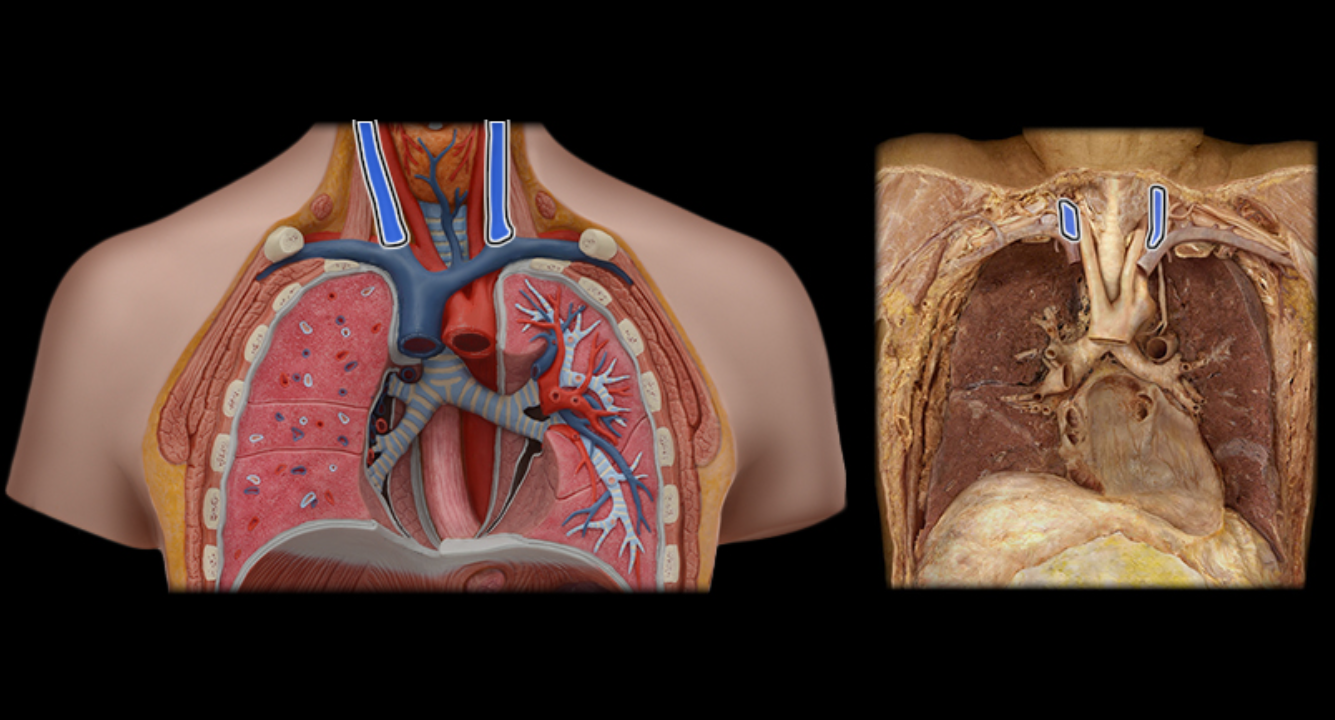

Arch of aorta

Brachiocephalic trunk

Pulmonary trunk

Superior vena cava

Ascending aorta

Pulmonary trunk

Pulmonary a.

Pulmonary vv.

Subclavian v.

Subclavian v.